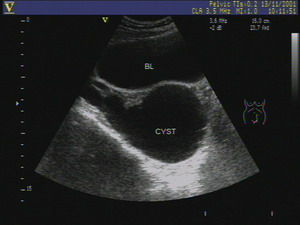

輸卵管的積水在超聲有能查出來的,主要是在輸卵管炎症的急性期,輸卵管的炎症造成傘端阻塞,炎症的滲出液積在輸卵管的管腔內使超聲顯示:子宮一側或雙側出現異常回聲輸卵管增粗,有的呈臘腸樣,管腔內呈低回聲或點狀回聲。

如圖所示為輸卵管超聲的B超圖象,BL是膀胱的圖象CYST是輸卵管積水的圖象。

但是輸卵管積水絕大多數是查不出來的。輸卵管積水是炎症引起的,但是炎症不會一直都在急性期,隨著炎症的發展膿液和裡面的水會被慢慢吸收掉剩下輸卵管傘端的一個空殼。空殼在B超上面是顯示不出來的。我們去看不孕的時候其實早已經過了輸卵管炎的急性期,所以說B超診斷輸卵管積水一局限性,很多時候查不出來。